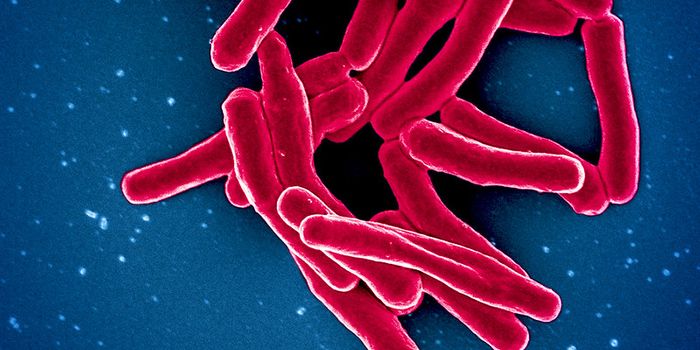

JUN 27, 2023Clinical & Molecular DXTuberculosis is still a major health problem in much of the world. It was the primary cause of death from an infectious ...

FEB 27, 2023MicrobiologyThe CDC has issued an alert about a rise in extensively drug-resistant (XDR) shigellosis, which causes gastrointestinal ...

FEB 13, 2023MicrobiologyAn outbreak of Marburg virus has killed nine people and sickened at least sixteen others in Equatorial Guinea's firs ...

JAN 29, 2023MicrobiologyWe share the world, and our bodies with bacteria. Many of those microbes are harmless or even beneficial, while some can ...